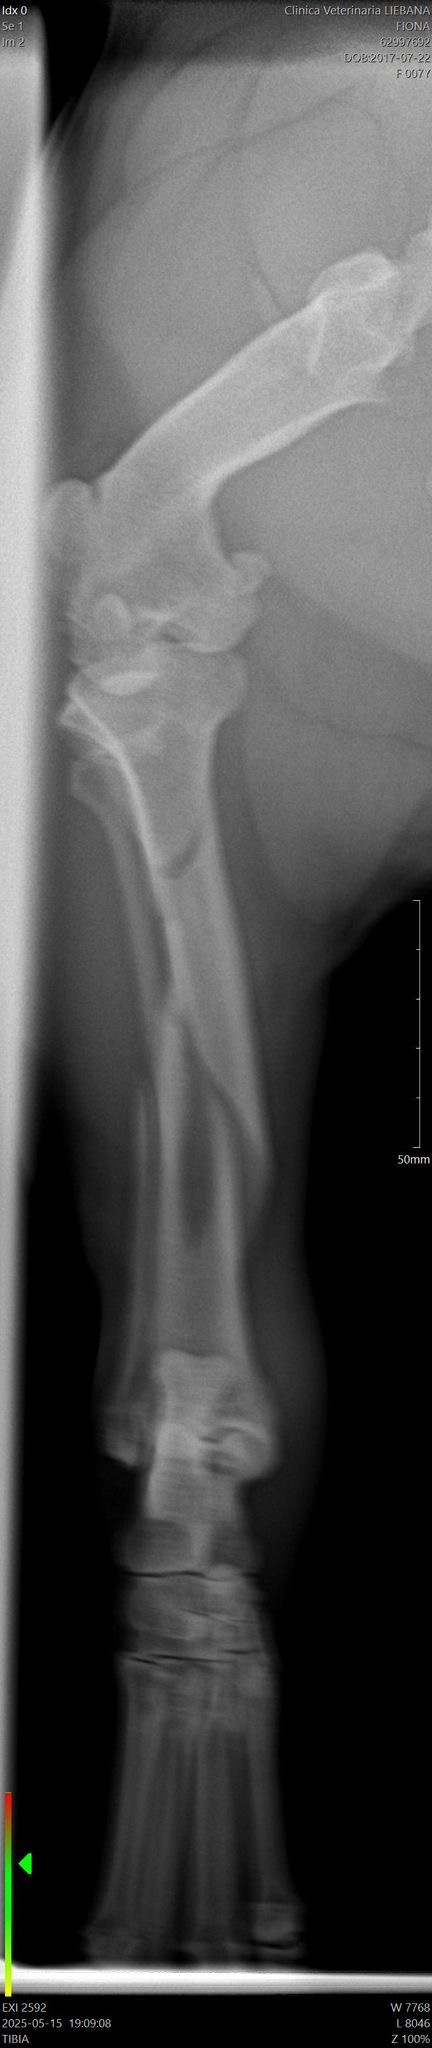

Hola, soy Fiona, soy una mini Bull terrier, tengo 7 años, soy muy cariñosa y sobretodo me gusta mucho jugar. La semana pasada, me rompí la patita, específicamente el fémur por lo que mi mamá me llevó al veterinario y le dijeron que era necesario hacerme una cirugía ya que con una escayola no podía repararse mi huesito.